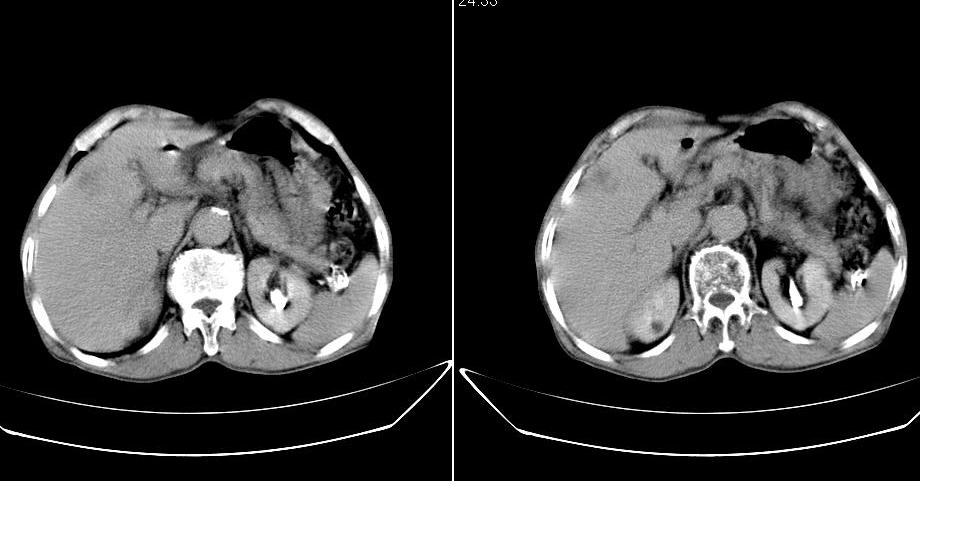

男,76岁,上腹部疼二天来就诊,彩超提示肝左叶占位,随后做上腹部ct平扫,今天做上腹部ct增强扫描,手工推药,效果不好,请谅解。

肝左叶s4肿块强化形式大概是:慢进慢出,逐渐强化----考虑血管瘤/腺瘤?{动脉期应更提前扫}。

肝右叶前段hcc

1)肝右叶前段低密度灶,不排除肝癌可能;建议查afp。2)右肾上极囊肿。

肝内胆管积气扩张,胆囊增大,肝右前叶低密度灶,逐渐强化,一元论,胆系感染,局限性肝脓肿;右肾囊肿。

考虑肝s4段肝脓肿可能?未排除肝癌。右肾上极囊肿。